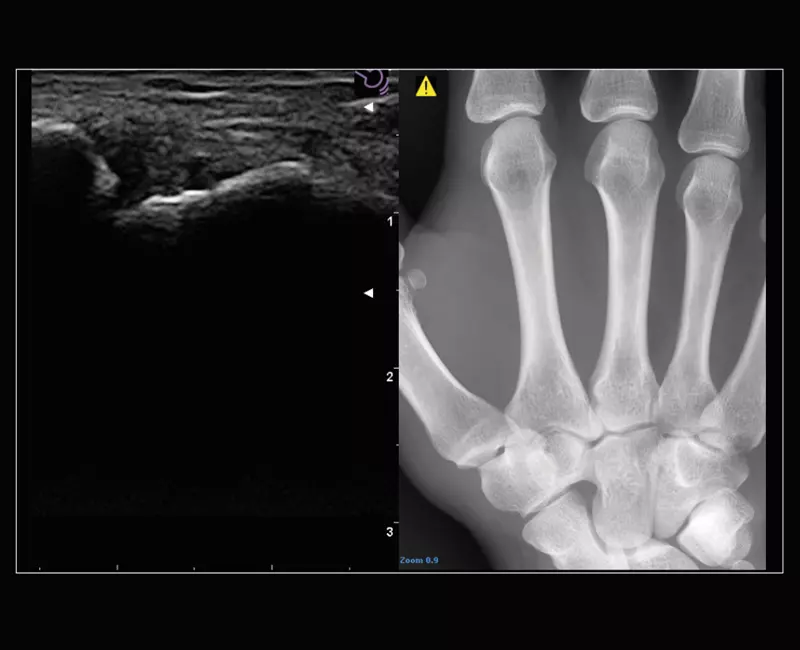

MyLab™9 Platform - MSK BodyMap and real-time XFlow on X-Ray extremities

MyLab™9 Platform - MSK BodyMap and real-time XFlow on X-Ray extremities